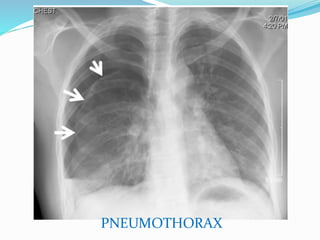

PNEUMOTHORAX

2e question : pneumothorax ?

 Un petit pneumothorax : peut être difficile à voir.

 Radioghraphie thoracique debout : visibilité la

plèvre viscérale, région de l`apex pulmonaire, pas de

vaisseaux entre cette ligne et la paroi thoracique.